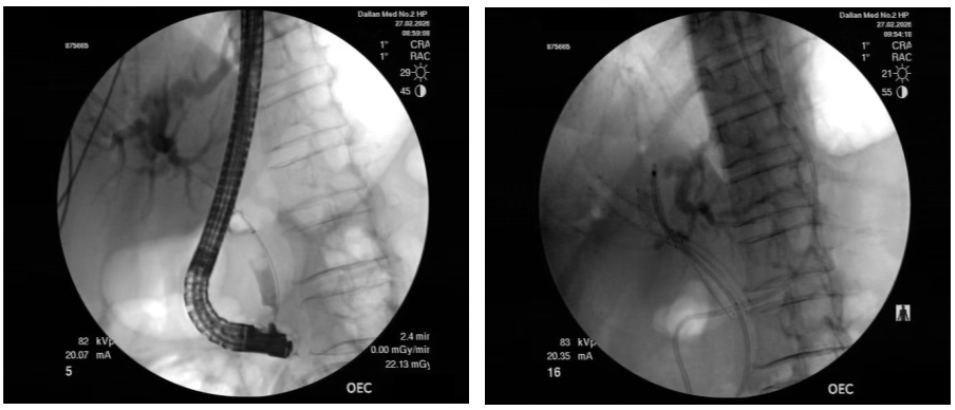

入院后,科室团队完善CT、MRI、胆道成像等检查,全面评估肿瘤侵犯范围及肝功能储备,严格排除内镜手术禁忌。经全科术前讨论,结合国际最新临床研究进展及患者实际情况,制定个性化内镜微创方案。在充分告知病情、治疗方案、预期疗效及风险后,团队为患者实施内镜下射频消融+胆道双金属支架置入术。手术在透视引导下精准完成导丝超选双侧肝管、射频消融肿瘤组织及双金属支架置入等关键步骤,术后患者安全返回病房。

肝门部胆管癌因其解剖位置特殊,被公认为胆道外科领域的技术高地——肿瘤位于左右肝管汇合处,常侵犯双侧肝管,导致肝门部结构紊乱,对于无法手术切除的肝门部胆管癌进行ERCP下支架引流的难度较大。操作者需要在透视下将导丝分别超选进入狭窄的左右肝管系统,这一步既关键也充满挑战,而随后胆管支架的置入也关系到患者的预后。

临床研究显示,金属支架中位通畅期更长,可延长患者生存期[1]。双金属支架置入需在透视下精准超选双侧肝管,技术门槛高,需经验丰富团队配合。此次手术采用双金属支架,实现“一次植入,长期获益”,既持久解除梗阻性黄疸,又为后续抗肿瘤治疗创造条件。